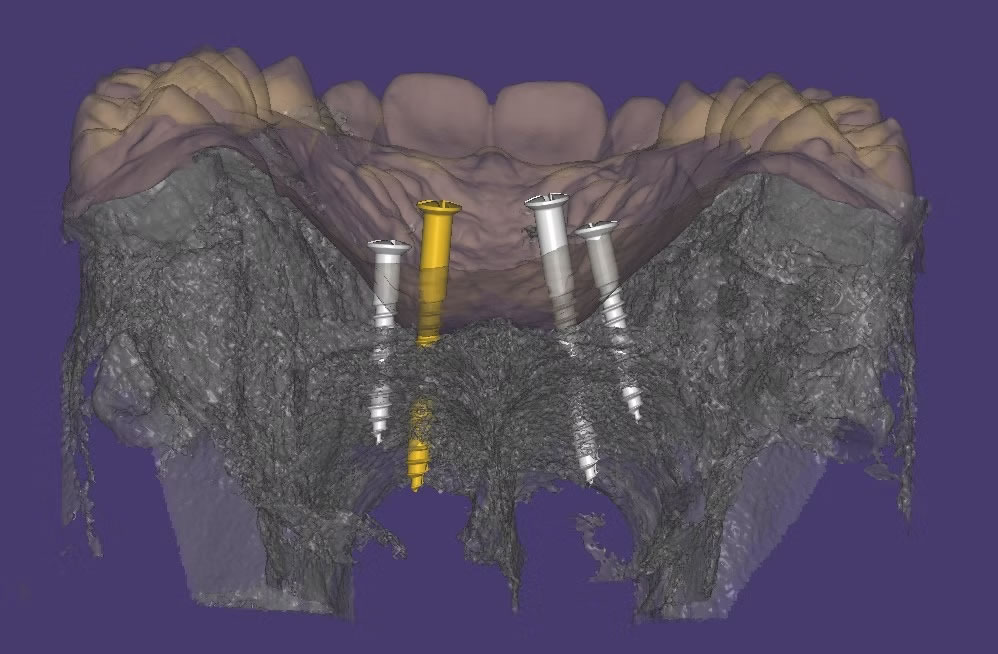

DISYUNTOR MARPE SINTERIZADO

ESTUDIOS CBCT

DISYUNTORES SINTERIZADOS